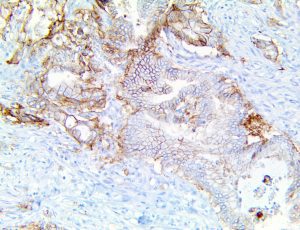

It is the ICU physician who is most likely to witness one of the deadliest manifestations of the abnormal immunological response, the cytokine storm syndrome (CSS). This response is also referred to by some as the cytokine release syndrome (CRS). CSS is characterized by continuous activation and expansion of macrophage and lymphocyte populations, which secrete large amounts of cytokines, causing the cytokine storm. This massive cytokine release is akin to hemophagocytic lymphohistiocytosis (HLH) disease, a syndrome characterized by initial unchecked and persistent activation of cytotoxic T lymphocytes and NK cells.

Clinical and laboratory manifestations of HLH include fever, enlarged liver and/or spleen, neurologic dysfunction, coagulopathy, liver dysfunction, cytopenias (i.e., low levels of erythrocytes, leukocytes, and/or platelets), hypertriglyceridemia, hyperferritinemia, hemophagocytosis, and eventually diminished NK cell activity as the immune system becomes progressively paralyzed. HLH can be familial (primary HLH) or secondary to another disease process (sHLH), such as rheumatic disease, in which it is referred to as macrophage activation syndrome (MAS, characterized by elevated ferritin).

This activation induces inflammatory monocytes to highly express IL-6, starting a localized and then systemic cascade effect that results in hyperproduction of IL-6, which accelerates the inflammatory process. Because IL-6 also increases vascular permeability, excessive levels cause blood vessels to become very leaky. This, along with clotting factors released from vascular endothelial cells, stimulates the coagulation cascade, resulting in microthrombosis (tiny clots), which leads to ischemia and tissue death of the kidney, intestines, heart, liver, brain and extremities.